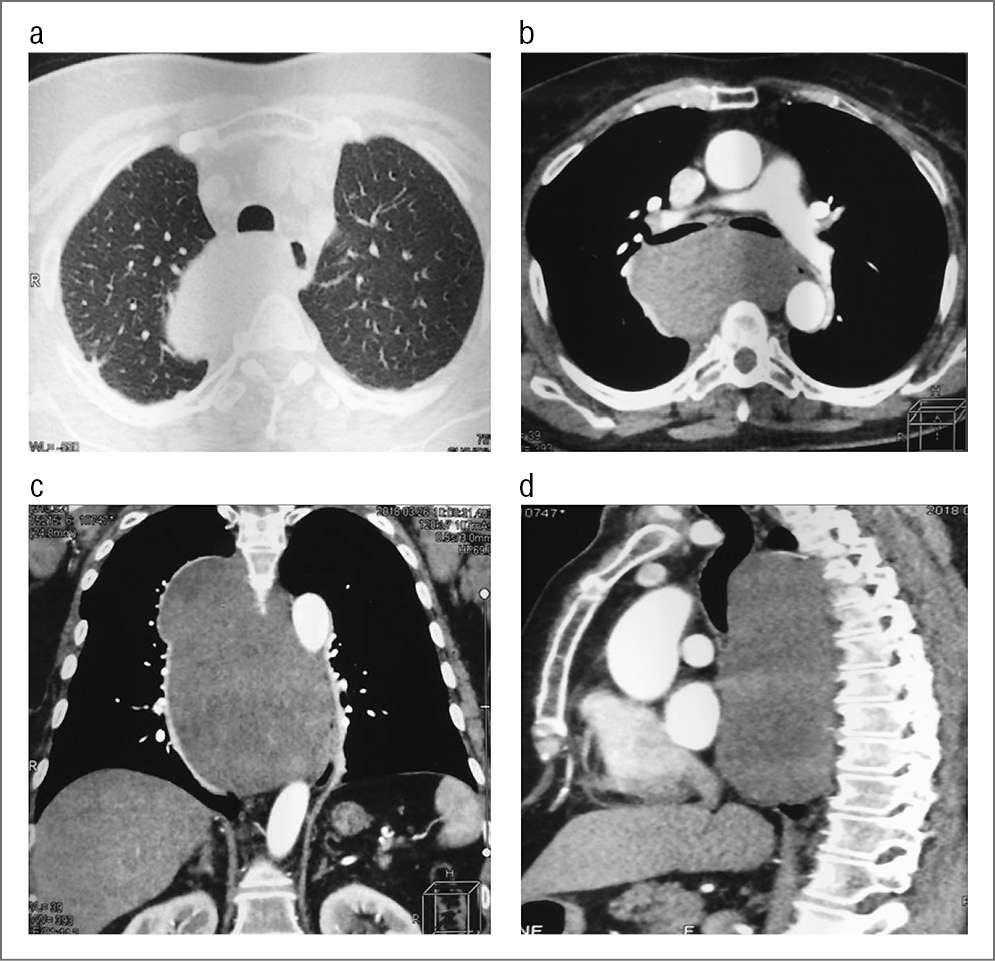

По объективным критериям термин «внутригрудные гигантские опухоли» является собирательным понятием, объединяющим в группу новообразования различной гистологической принадлежности, объединенных одной анатомической областью, и диаметром, равным или превышающим 20 см [1], что приводит к сходному клиническому проявлению (рис. 3) [2]. Именно поэтому не существует в общепринятом понимании классификации гигантских новообразований грудной клетки. Практикующими хирургами-онкологами ФГБУ «НМИЦ онкологии им. Н.Н. Блохина» определены размеры и распространенность внутригрудных гигантских образований [3].

Рис. 3. МСКТ. Гигантское образование правого гемиторакса с дислокацией органов средостения в левую плевральную полость: а – аксиальная проекция; b – 3D-реконструкция.

Пациентка Ч., 64 года. Диагноз: гигантская невринома правого гемиторакса, осложненная компрессионным синдромом, дислокацией сердца в левую плевральную полость; правосторонний гидроторакс; синдром верхней полой вены; легочная гипертензия; хроническая сердечно- легочная недостаточность. Жалобы на одышку при средней физической нагрузке, отеки нижних конечностей, невозможность спать на спине в горизонтальном положении, снижение массы тела. Анамнез: считает себя больной с 46 лет, когда при проведении рентгенографии выявлено новообразование нижней доли правого легкого малых размеров. Наблюдалась у онколога по месту жительства. В настоящее время стала отмечать появление одышки при средней физической нагрузке, отеки нижних конечностей. По данным МСКТ выявлено гигантское образование правого гемиторакса с дислокацией органов средостения в левую плевральную полость. При контрастировании визуализировались компримированные легочные сосуды. Наиболее показательно это видно при построении 3D-изображения (см. рис. 3, а, b). В отделении торакальной хирургии УКБ №1 проведена операция: переднебоковая торакотомия по четвертому межреберью с пересечением выше- и нижележащих ребер. Опухоль вывихнута в рану, удалена. Масса опухолевого узла – 2500 г. Гистологическое исследование: невринома (см. рис. 4).